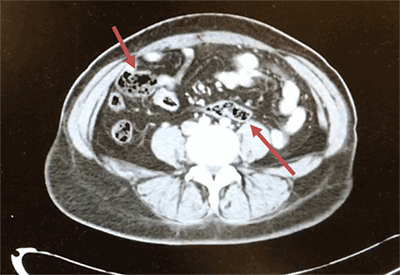

A 48-year-old female with a past medical history of diabetes mellitus presented with abdominal pain. She reported that for the past two days, she had worsening abdominal pain. The pain was localized to her right and left lower quadrants, without radiation and not associated with oral intake. The pain was rated 8/10 and was described as a sharp pain that was constantly present. She also complained of chills and nausea, but no vomiting. She denied diarrhea, any recent falls or injury, and any exposure to ill contacts. On physical exam, her vital signs were pulse 83, respirations 18 and blood pressure 102/59. The abdomen was soft, without rebound or guarding. A positive McBurney’s point and positive obturator sign was noted, with a negative Psoas sign. On admission, her white blood cells were normal at 5.7 but trended up to 18.7 about 14 hours afterwards. Her hemoglobin, and basic biochemistry panel were within normal limits. CT of the abdomen and pelvis with contrast showed findings consistent with acute distal appendicitis. The distal 3 cm of the appendix was thickened to 1.3 cm, fluid-filled and showed adjacent stranding. The segment of distended appendix was seen located within the right anterior paracentral pelvis approximately 3 cm above the umbilicus (Figure 1 and Figure 2). We can also see the sigmoid colon on the right and cecum in the middle of the body (Figure 3).

Figure 2. Vermiform appendix shown in paracentral pelvis